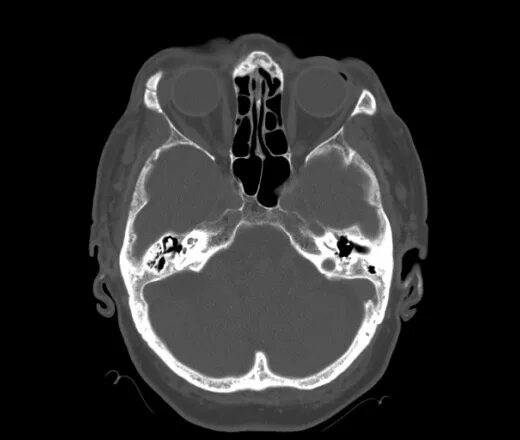

Череп на кт